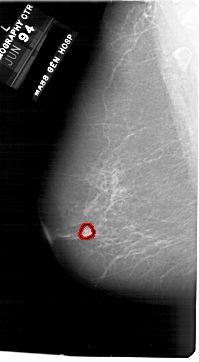

A_1750_1.RIGHT_MLO

RIGHT_MLO LINES 6871 PIXELS_PER_LINE 3826 BITS_PER_PIXEL 12 RESOLUTION 43.5 NON_OVERLAY

FILE: A_1750_1.LEFT_CC.OVERLAY

TOTAL_ABNORMALITIES 1

ABNORMALITY 1

LESION_TYPE MASS SHAPE ROUND MARGINS CIRCUMSCRIBED

ASSESSMENT 3

SUBTLETY 4

PATHOLOGY BENIGN

TOTAL_OUTLINES 1

BOUNDARY